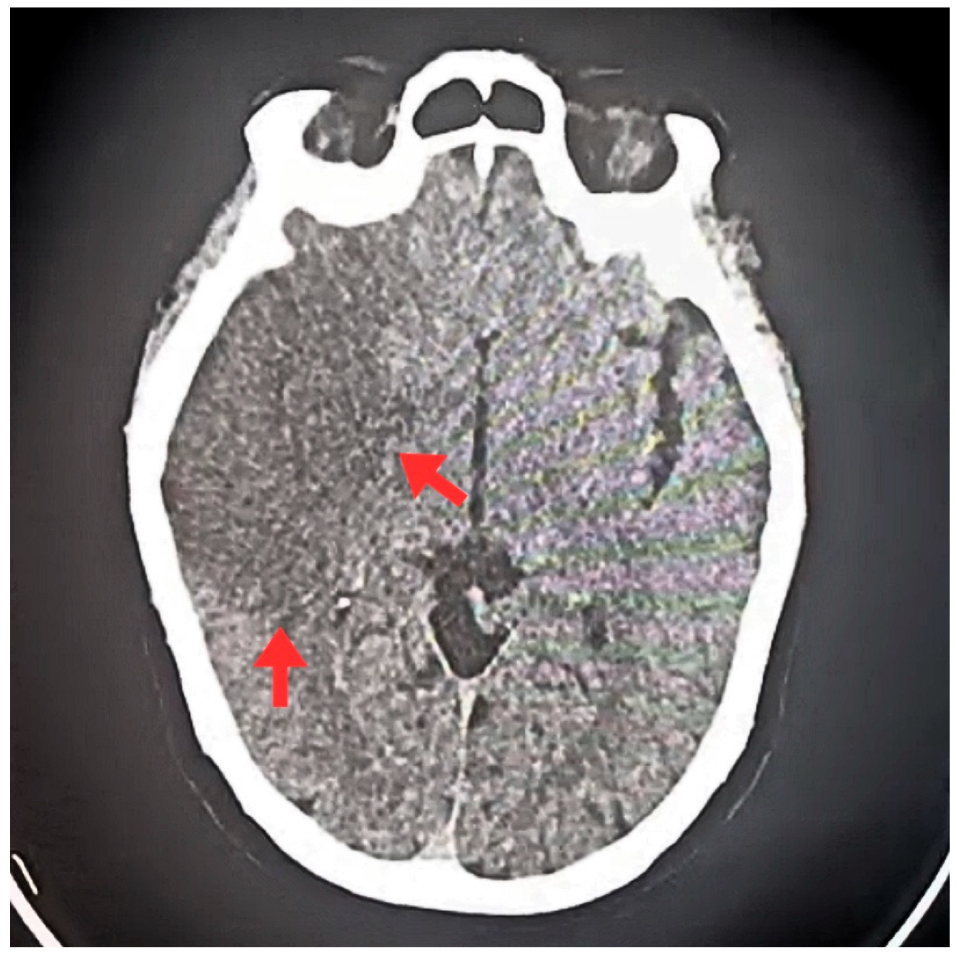

| T0 + ED arrival | Emergency Dept. | Stroke code activated. NIHSS 9, GCS 11/15, premorbid mRS 0. | ECG: typical atrial flutter with rapid ventricular response. Non-contrast CT brain: right MCA ischemic stroke (ASPECTS 7), no hemorrhage. | Supportive acute stroke care | Acute ischemic stroke suspected/confirmed |

| Early inpatient workup (Day 0) | Hospital | Suspected cardioembolic source in context of arrhythmia/Chagas cardiomyopathy. | TTE: severe LA dilation + mobile LA thrombus; LVEF 45%. Labs: no major abnormalities; mild troponin I and NT-proBNP elevation. | — | Cardioembolic mechanism supported |

| First 24 h | Hospital | Hemodynamic and neurological stability. | Follow-up CT: no hemorrhagic transformation. | Continue monitoring/management | No bleeding complications documented |